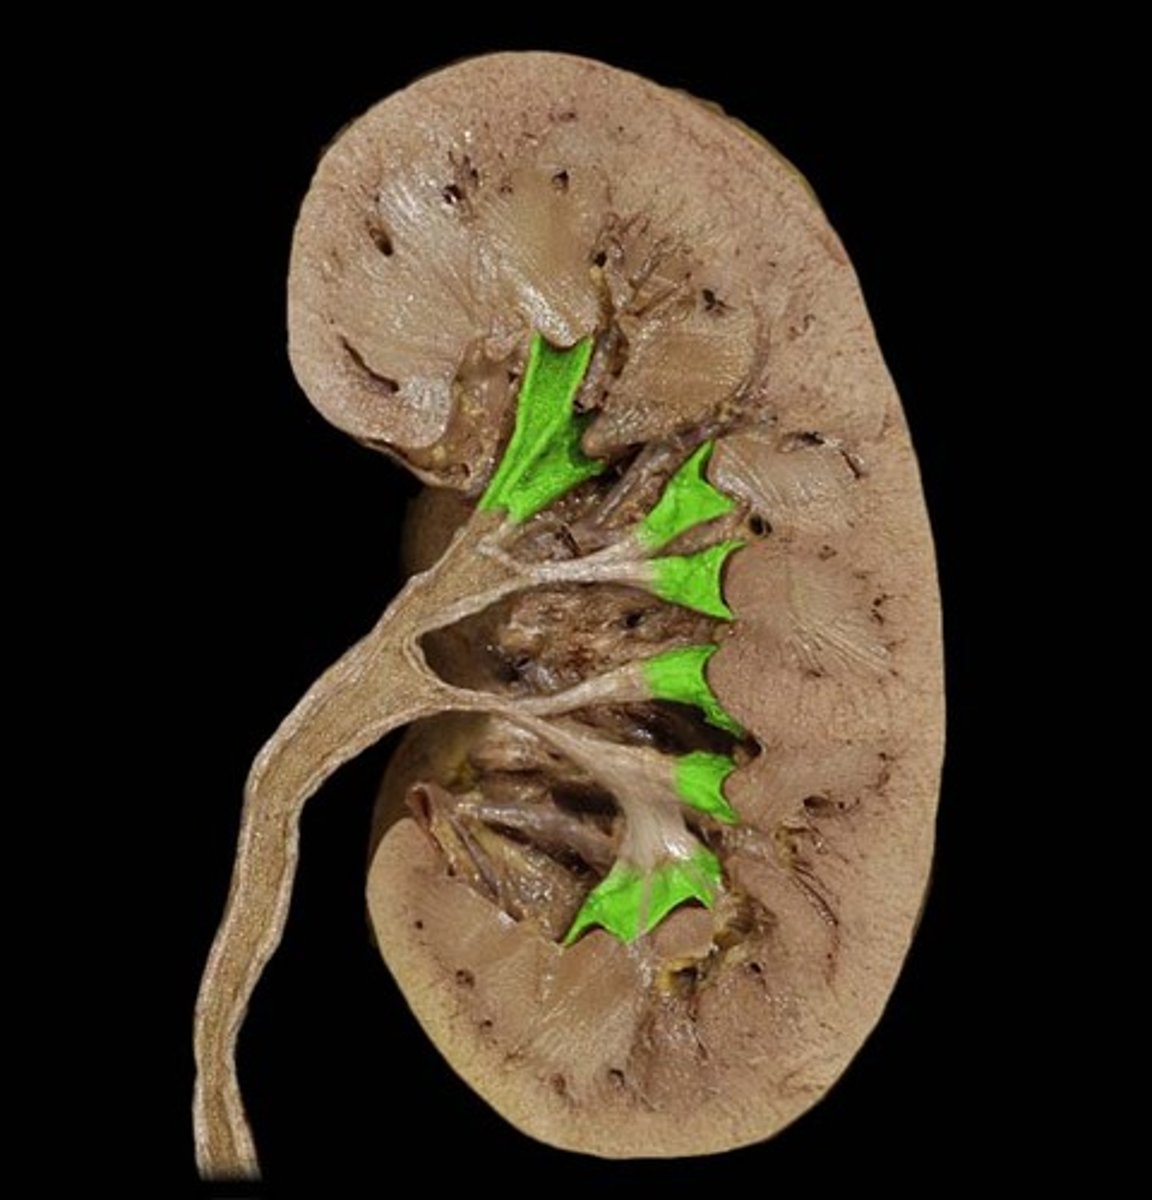

Renal columns

What is this?

Renal pyramids

Renal papillae

Minor calyx

Major calyx